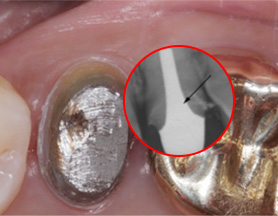

1년전 다른 치과에서 보철치료를 받은 부위에 지속적인 통증과

잇몸 염증으로 내원, 기존 보철물 수복시 신경관을 제대로 치료하지 못하여 염증이 재발된 상황이었습니다. 고운미소에서는 기존 포스트를 제거하고 오염된 부위에 약재를 삽입하여 염증을 제거하는 신경치료를 시행하였습니다.

지속적인 통증과 잇몸염증